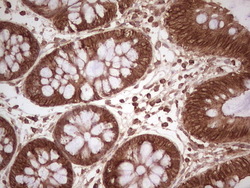

- Submitted by

- OriGene (provider)

- Main image

- Experimental details

- Immunohistochemical staining of paraffin-embedded Human colon tissue within the normal limits using anti-WIBG mouse monoclonal antibody. (Heat-induced epitope retrieval by 1 mM EDTA in 10mM Tris, pH8.5, 120C for 3min, TA806496)

- Validation comment

- IHC